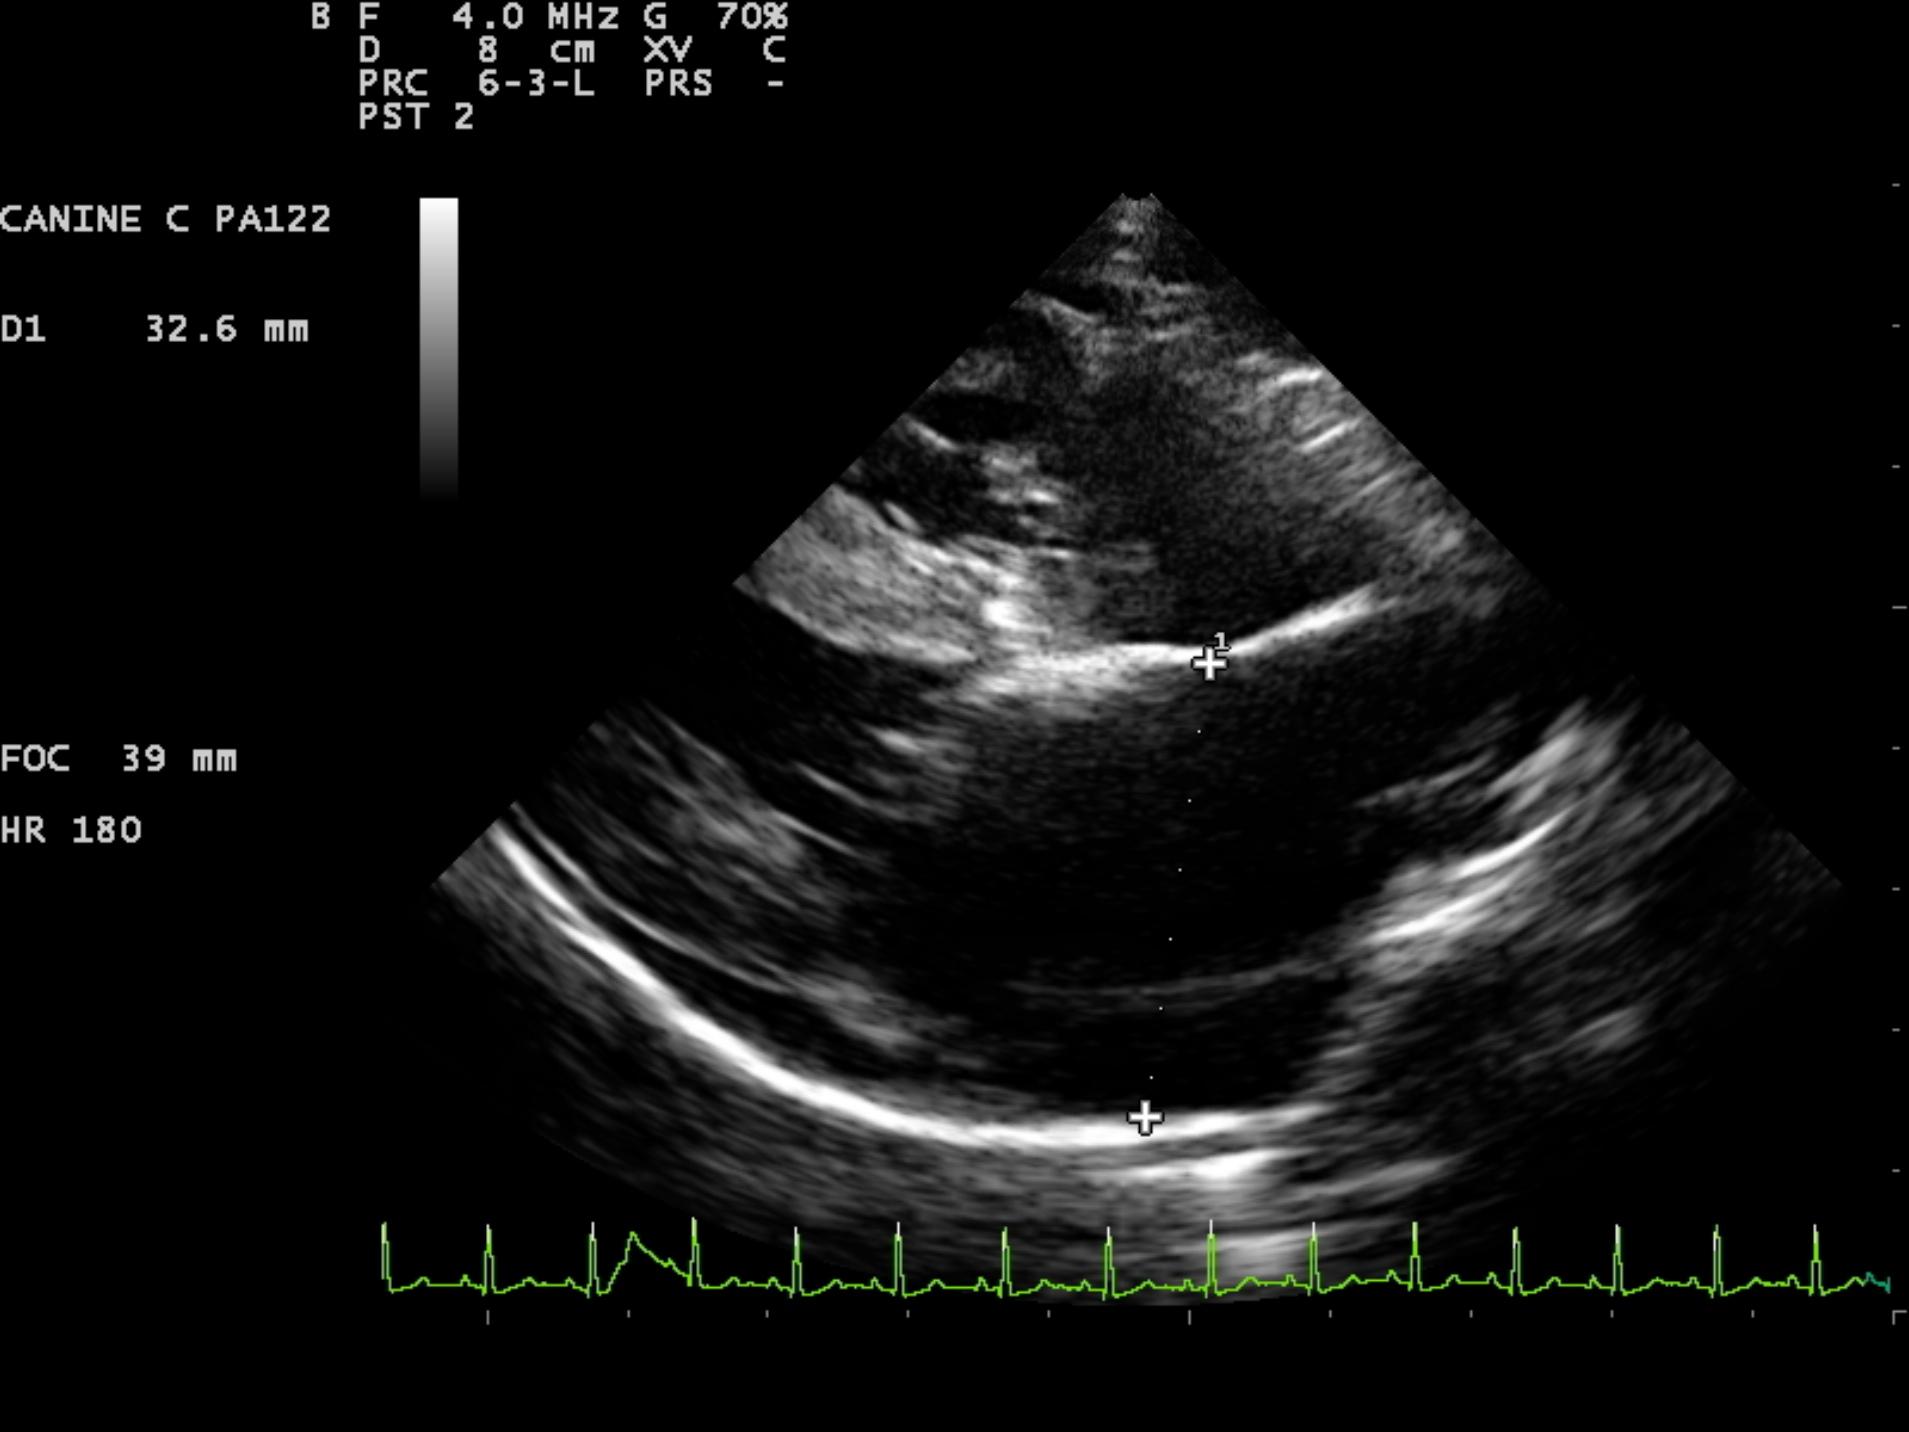

An 8-year-old F Maltese was presented for examination. A grade 5/6 systolic heart murmur was noted. Radiographs revealed severe generalized cardiomegaly and an unremarkable pulmonary parenchyma. Moderate hepatomegaly and ascites was additionally noted.